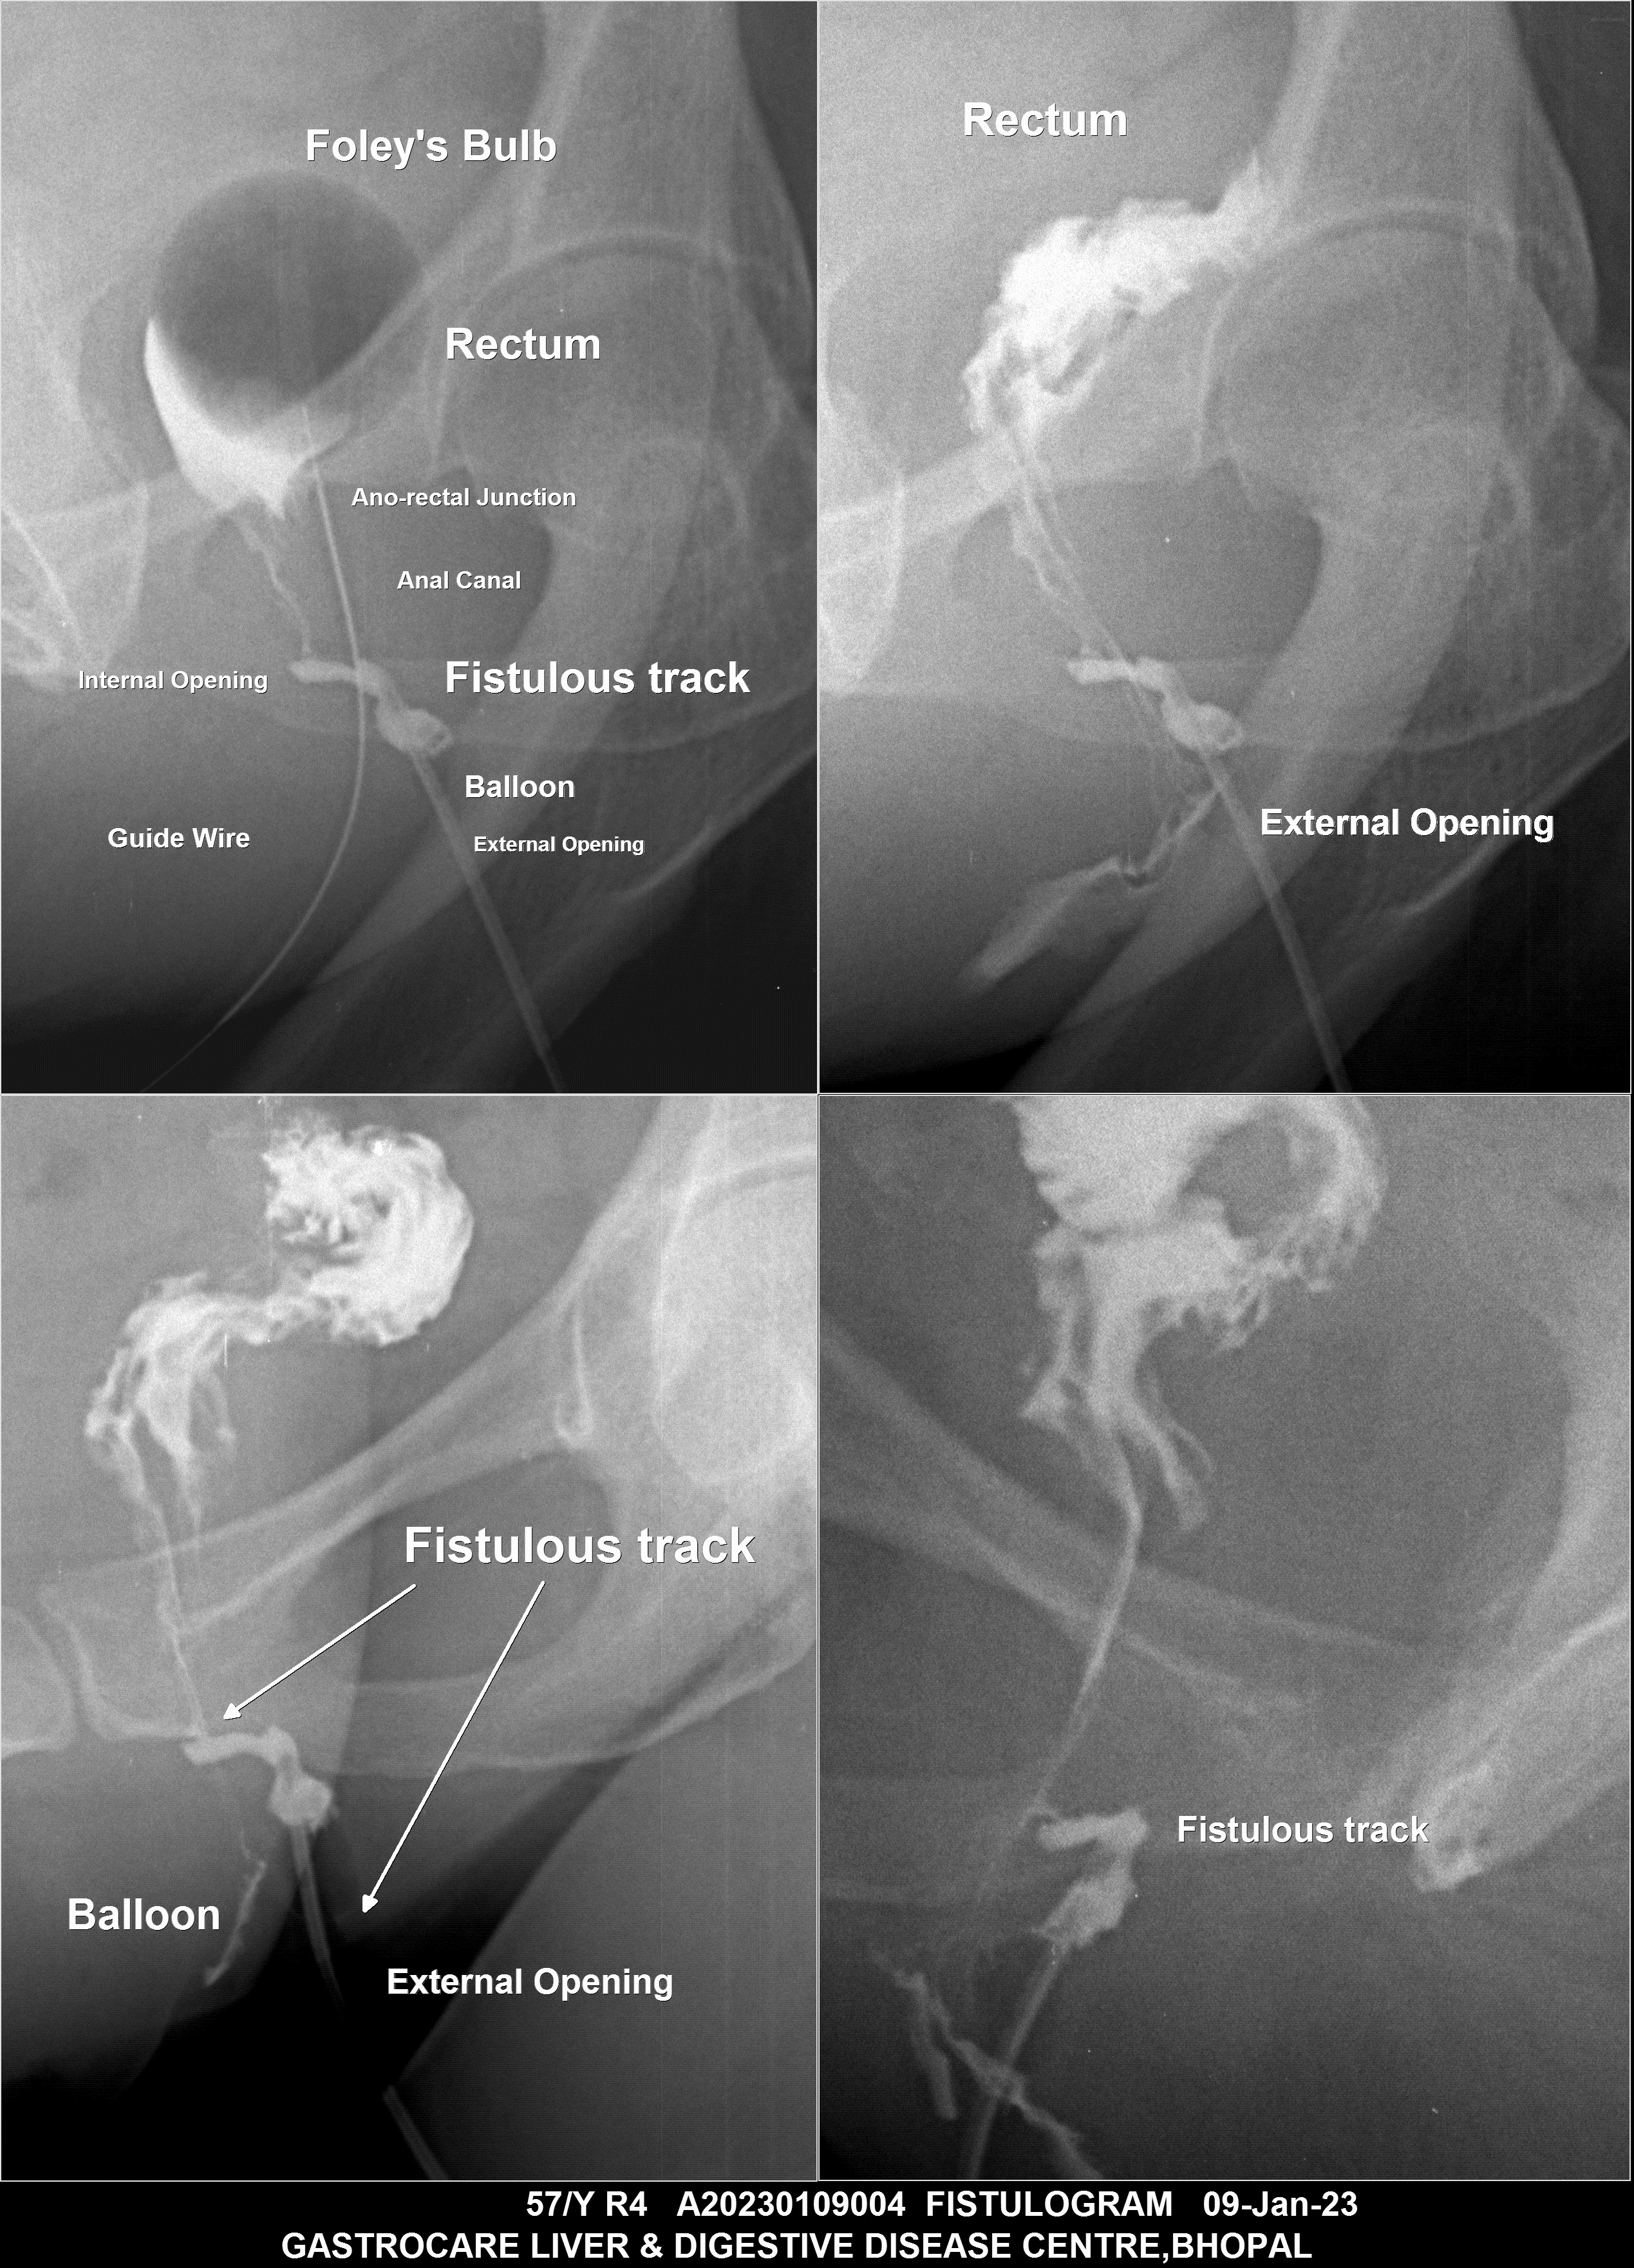

Section: FISTULOGRAM Total: 8 images